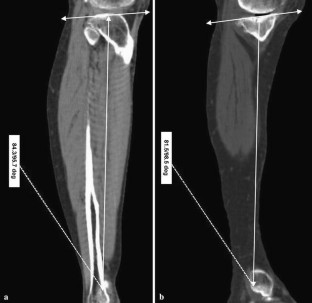

The authors aimed to demonstrate the relationship between the sagittal mechanical axis of the tibia and other reference axes of the tibia and fibula in patients with advanced osteoarthritis of the knee joints, and then to identify a reliable landmark in order to minimize posterior tibial slope measurement errors. We evaluated 133 osteoarthritic knees with neutral or varus deformity in 64 female and 8 male patients. Axial computed tomographic images of whole tibiae including knee and ankle joints were obtained and reconstructed using 3-dimensional imaging software. Angles between the mechanical axis (MA), the tibial anatomical axis (TAA), the anterior tibial cortex (ATC) and the fibular shaft axis (FSA) were measured, and then medial and lateral tibial slope angles were measured using all axes. Mean angles between MA and the other anatomical reference lines (TAA, ATC and FSA) were 0.9, 2.2 and −2.1°, respectively. The mean values of lateral tibial slopes with respect to MA, TAA, ATC and FSA were 8.7, 10, 12 and 7.3, respectively, and their intra- and inter-observer reliabilities were higher than those of medial tibial slopes. Although posterior tibial slope change markedly according to the reference axis used, the axes used in conventional TKA showed significant correlations with each other, and thus, may be used safely if differences with the mechanical axis are considered. Moreover, the lateral tibial slope might have advantages over the medial tibial slope in terms of restoration of the natural tibial slope.

Fig. 2